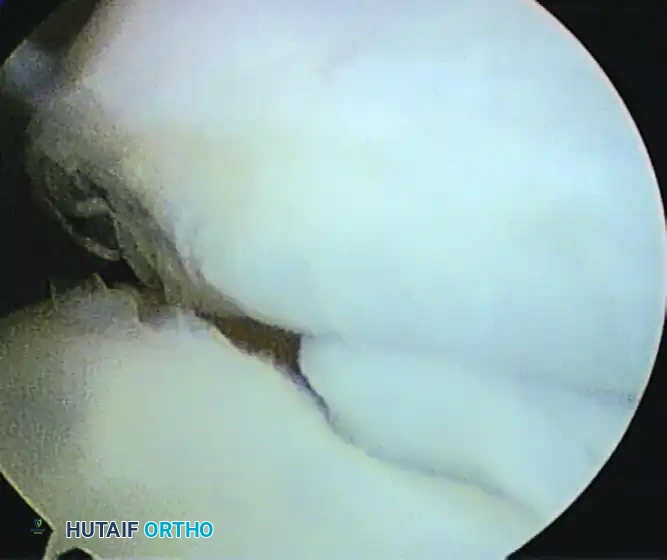

Figure 52-65 A: Arthroscopic view of a large, obstructing loose body situated in the anterior elbow compartment.

Figure 52-66: Arthroscopic visualization of a partially detached osteochondritis dissecans (OCD) lesion of the capitellum, demonstrating articular cartilage fissuring and instability.